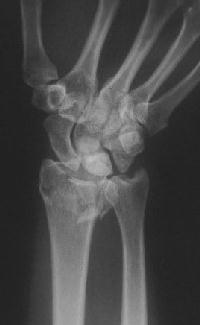

Clinical Example: Distraction plate fixation of distal radius fracture

A tricky case, for the patient previously had a large skin graft over the dorsal metacarpus / wrist / forearm. Incisions are marked here just before the plate was removed.